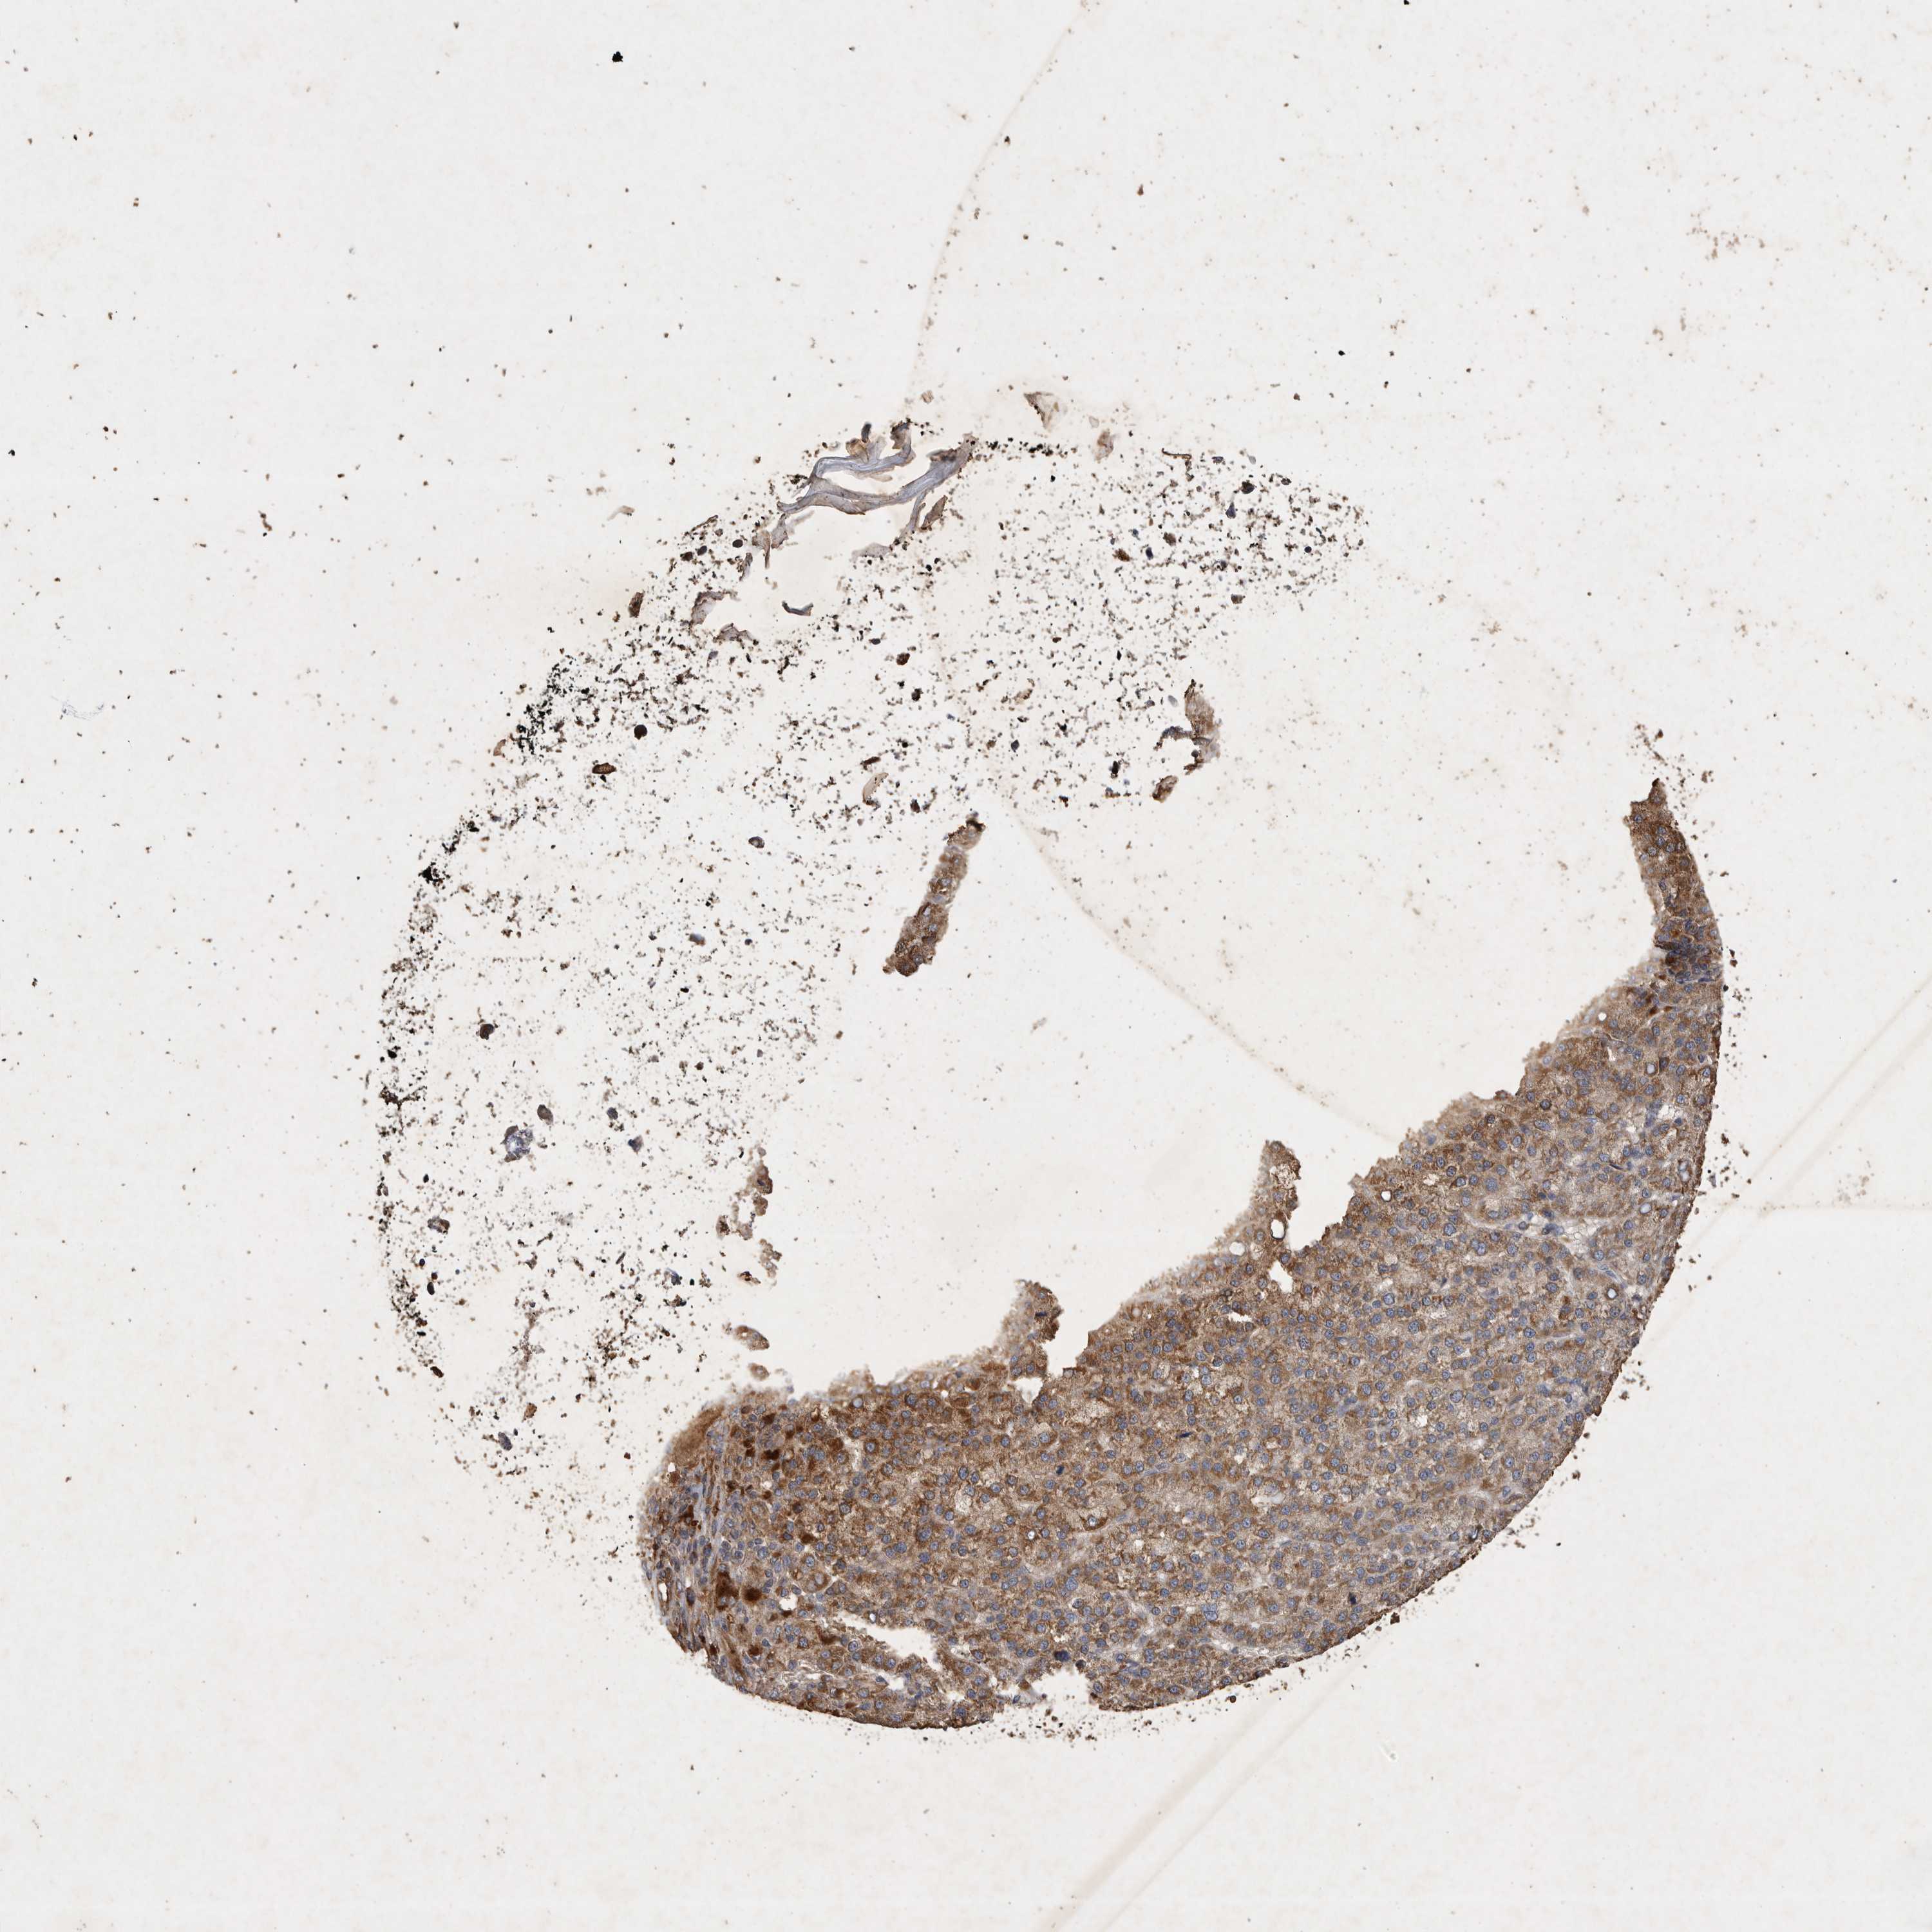

LIVER CANCER - Protein expressioni

A mouse-over function shows sample information and annotation data. Click on an image to view it in a full screen mode. Samples can be filtered based on level of antibody staining by selecting one or several of the following categories: high, medium, low and not detected. The assay and annotation is described here.

Note that samples used for immunohistochemistry by the Human Protein Atlas do not correspond to samples in the TCGA dataset.

Antibody stainingi

Antibody staining in the annotated cell types in the current human tissue is reported as not detected, low, medium, or high, based on conventional immunohistochemistry profiling in selected tissues. This score is based on the combination of the staining intensity and fraction of stained cells.

Each image is clickable and will lead to virtual microscopy that enables deeper exploration of all samples and also displays staining intensity scores, fraction scores and subcellular localization as well as patient and tissue information for each sample.

Antibody HPA024550

Antibody HPA027160

Staining

High

Medium

Low

Not detected

Intensity

Strong

Moderate

Weak

Negative

Quantity

>75%

75%-25%

<25%

None

Location

Nuclear

Cytoplasmic/membranous

Cytoplasmic/membranous,nuclear

Cholangiocarcinoma

Carcinoma, Hepatocellular, NOS